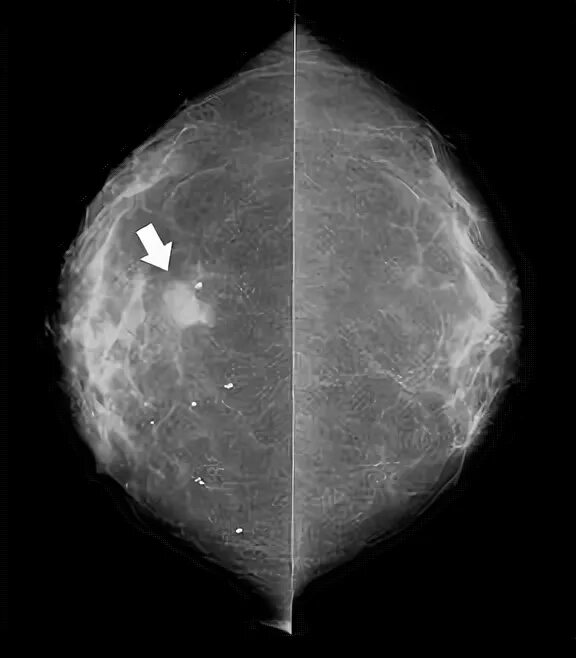

Склерозирующий аденоз молочных желез